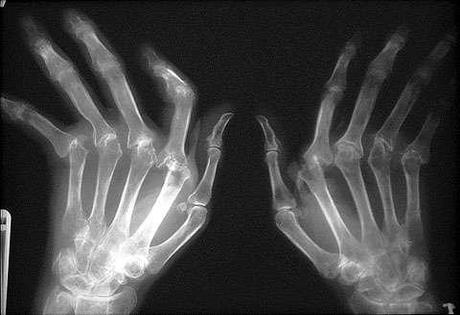

Además, esta enfermedad suele aparecer de forma simétrica. A lo largo del tiempo suele provocar pequeñas erosiones, llegando incluso a la desaparición del cartílago que funciona como almohadilla evitando el rozamiento de los huesos.

Los síntomas más habituales de la artritis reumatoide son el dolor, hinchazón y sensación de rigidez. Si concretamos más aún, los miembros más afectados son las muñecas, los nudillos, las articulaciones de los dedos, los hombros, los codos, las caderas, las rodillas, los tobillos y los dedos de los pies y la cadera.

En cuanto al síntoma de la sensación de rigidez, esta suele ser matutina y suele durar entre 45 y 60 minutos. Los dedos pueden llegar a deformarse.